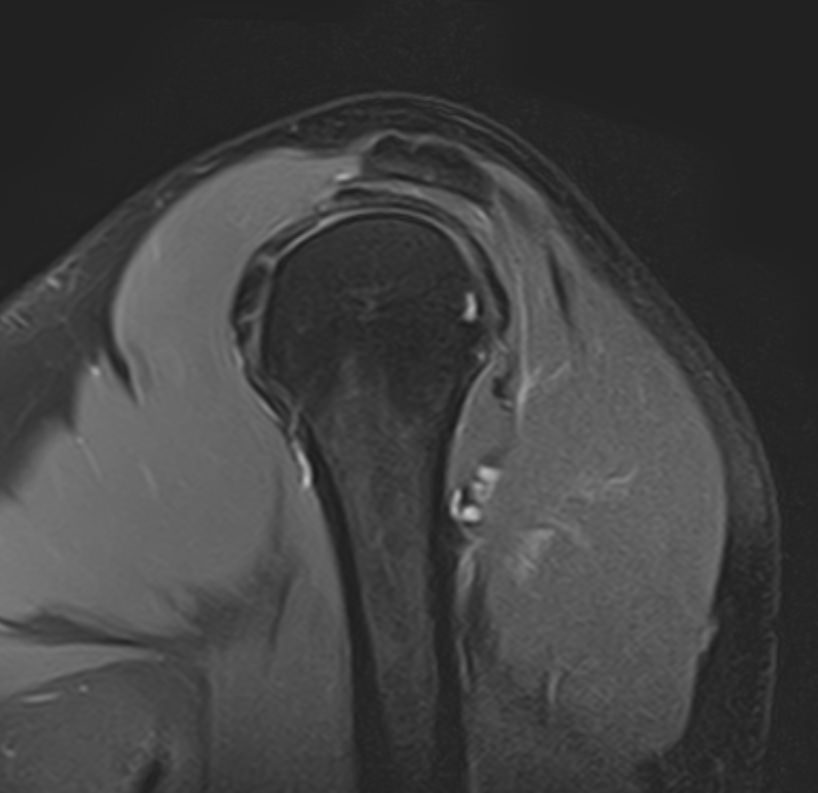

Для того, чтобы оценить состояние шейных позвонков с прилегающими тканями и одновременно визуализировать плечевой сустав, в нашей клинике выполняется комплексное обследование, включающее два протокола: МРТ шейного отдела позвоночника и МРТ плечевого сустава.

Метод МРТ позволяет оценить состояние всех анатомических областей шейного отдела позвоночника: костную структуру позвонков, спинной мозг с отходящими от него нервными корешками и окружающие мягкие ткани. Протокол обследования плечевого сустава включает оценку костной структуры, суставной капсулы, полости сустава с выстилающей его синовиальной оболочкой, связок, сухожилий, мышц и окружающих мягких тканей.